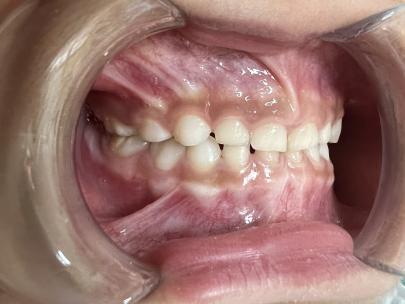

案例一:

治疗后